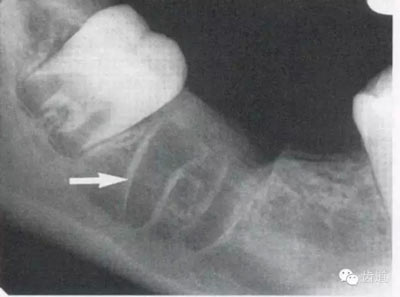

由升支前緣下部斜向前下方,為一密度高的帶狀影像。常重疊在第二、三磨牙牙冠處、頸部或根部,使牙髓室或根管不能清晰顯示